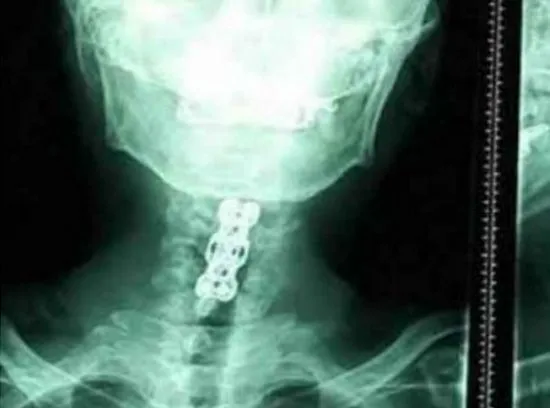

นายหวังถูกเพื่อนนำส่งโรงพยาบาลโดยทันที หลังจากตรวจเช็คแล้วพบว่า กระดูกสันหลังบริเวณคอสั่น ทำให้สมองมีเลือดออก หมอกระดูกยังบอกอีกว่า “เมื่อกี้ตรวจเช็คแล้วขาทั้งสองข้างไม่สามารถขยับได้ มีเพียงแค่แขนสองข้างที่สามารถยกขึ้นมาได้นิดหน่อย” หลังเอ็กซเรย์พบว่า กระดูกที่คอบางจุดหัก มีความเสี่ยงที่จะเป็นอัมพาตทั้งตัวสูงมาก ต้องผ่าตัดโดยด่วน

คุณหมอยังกล่าวอีกว่า การเงยหัวบ่อยๆไม่ได้ทำให้มีอาการเหล่านี้ได้ แต่เนื่องจากนายหวังดื่มน้ำอัดลมบ่อยๆ จึงทำให้กระดูกและเส้นเอ็นค่อยๆชา และคลายออกจากแกนกลาง จนทำให้เป็น “โรคเส้นประสาทไขสันหลังส่วนคอเสื่อม” ในเครื่องดื่มประเภทนี้มีส่วนประกอบของปริมาณน้ำตาลมาก เมื่อดื่มเป็นเวลานานจะทำให้ “ขาดโพแทสเซียม” จะทำให้ร่างกายไม่มีเรี่ยวแรง